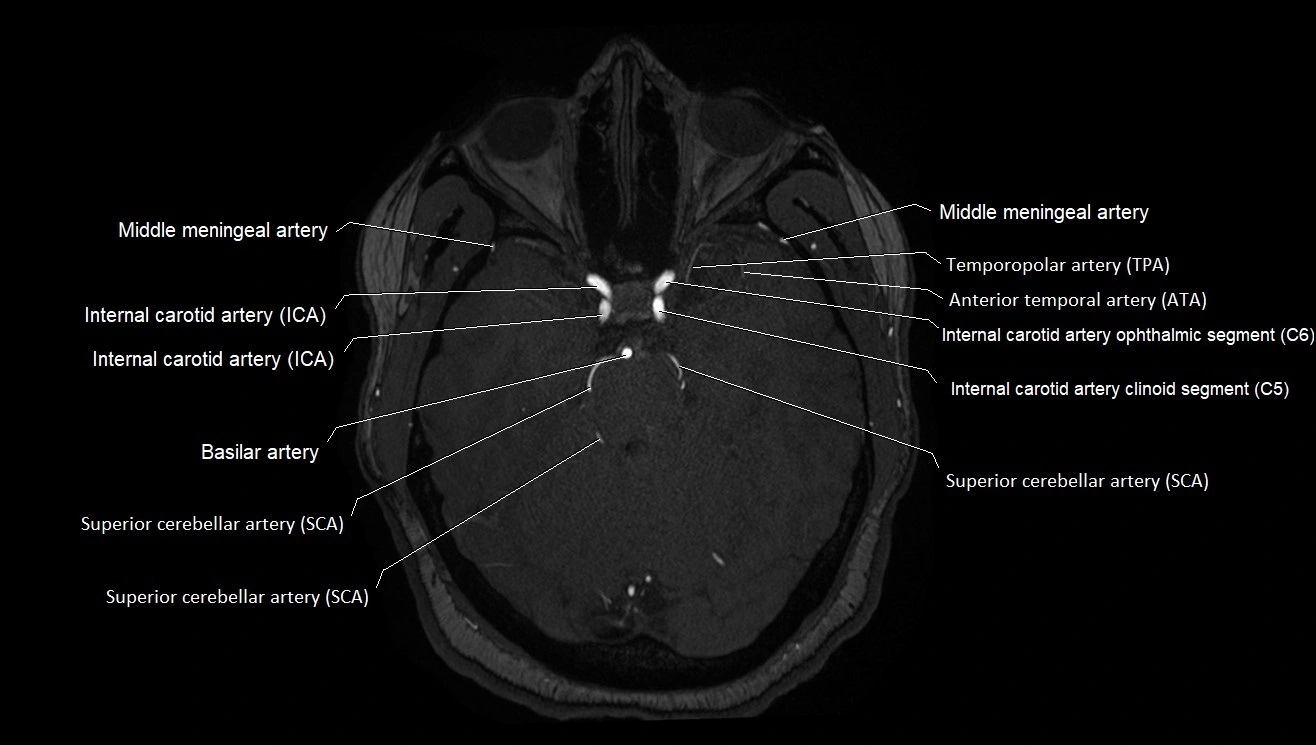

CTA (CT Angiography):

• Opacified with iodinated contrast, AChA appears as a bright high-attenuation vessel

• Visualized from ICA origin along optic tract toward choroid plexus

• 3D reconstructions depict its course and relation to adjacent arteries

• Gold standard for identifying aneurysms, occlusion, or vascular anomalies

CT images

image